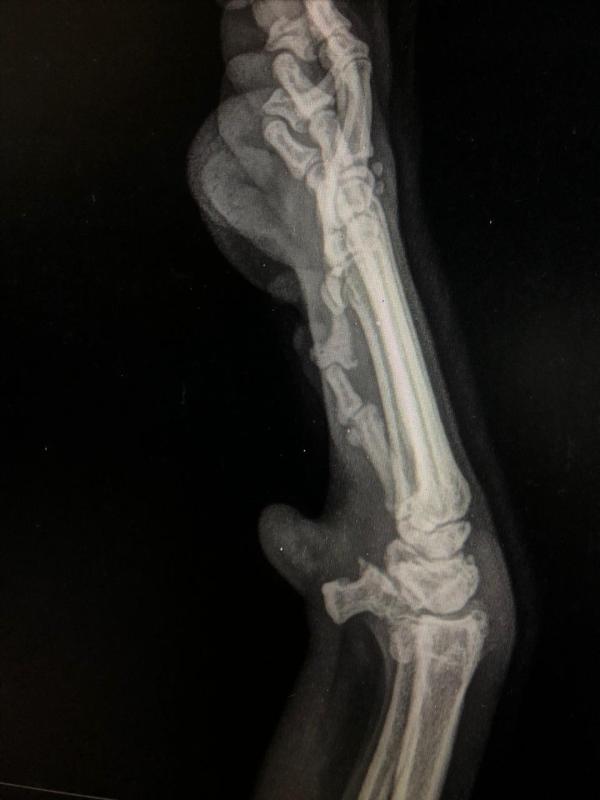

Sin embargo, no siempre son efectivos para aliviar los síntomas o prevenir la aparición de todas las enfermedades mencionadas, puesto que entran en juego muchos factores como el hereditario o el congénito. Así, en el caso de la displasia, por ejemplo, si se produce por una malformación de nacimiento, los condroprotectores no podrán actuar, mientras que si el problema surge por desgaste de la articulación, sí se recomienda su uso. Por este motivo, los expertos apuntan que la eficacia de estos medicamentos se observa, sobre todo, en perros con artrosis.

hola, tengo un pastor belga malinois de 4 meses, y viene presentando hace mas menos 1 mes una deformidad en valgo de ambas muñecas, que ha aumentado con el paso del tiempo, para la cual su veterinaria recomendo el uso de un complemento vitamínico el cual tiene condroitina, glucosamina, y otras vitaminas y minerales, y tambien dice de ponerle calcio, porque esta deformidad puede deberse entre otras cosas a un deficit de calcio, pero he leido varios articulos y consultado con otras personas y dicen de no poner calcio para tratar este tipo de deformidades,